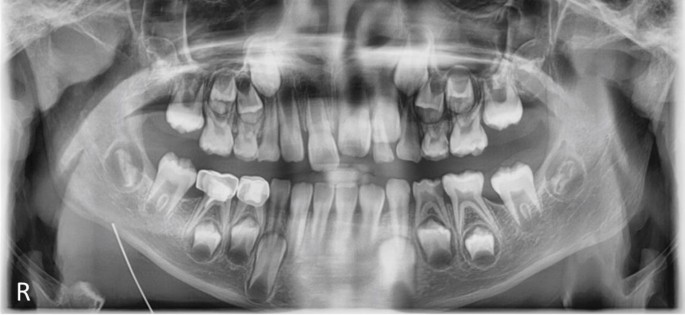

A conservative monitoring approach was adopted. At eight-month follow-up (precise age: eight years eight months), the mandibular right FPM (46) had erupted clinically. Repeat radiography (Fig. 2) demonstrated accelerated development of the marked teeth compared to premolars at Nolla stage 7, confirming they were delayed FPMs rather than second molars. The remaining FPMs showed crowns positioned submucosally above the alveolar crest, with anticipated natural eruption.